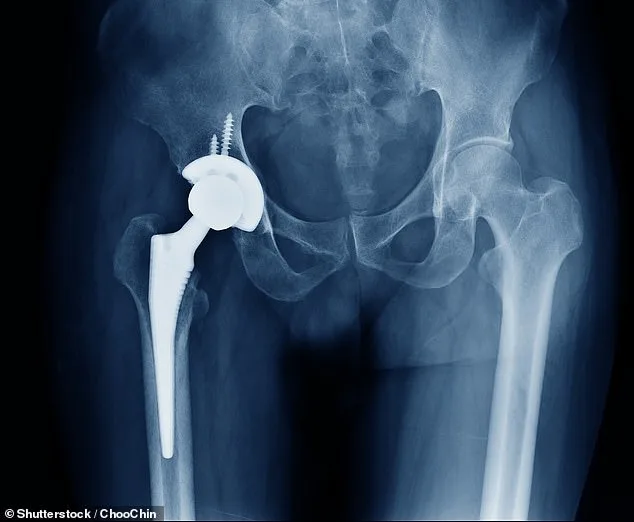

A critical machine failure at a global supplier of bone cement has triggered a major disruption in the UK's National Health Service (NHS), threatening to cancel nearly a million joint replacement surgeries. The shortage, caused by Heraeus — the NHS's preferred provider — has left only a week's worth of supply remaining. Hospitals across England are now instructed to cancel non-urgent procedures, with over 850,000 patients currently waiting for knee or hip replacements. The crisis has forced officials to prioritise emergency cases, including elderly patients with hip fractures, despite over 22,000 individuals having waited more than a year for treatment.

The situation has sparked concern among medical experts and patient advocacy groups. Arthritis UK has described the shortage as a 'crushing blow,' warning that wait times could revert to levels seen during the pandemic. The British Orthopaedic Directors Society and the British Orthopaedic Association have advised NHS trusts to focus on trauma and urgent cases, highlighting the limited availability of alternative cement suppliers. In 2024 alone, around 200,000 first-time knee and hip procedures relied on bone cement, a critical component that helps secure implants and expedite patient recovery.